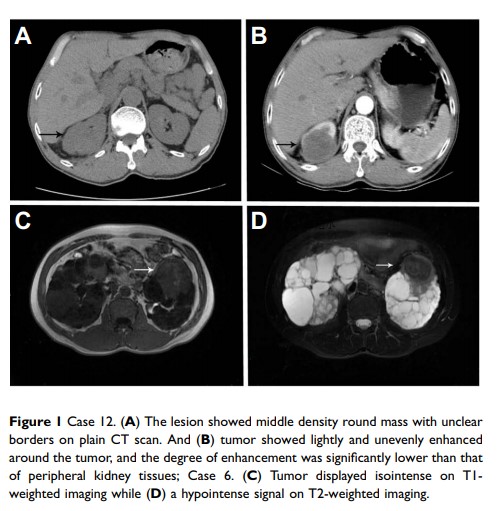

肾集合管癌的临床特征和预后结果:来自单一机构的 12 个病例